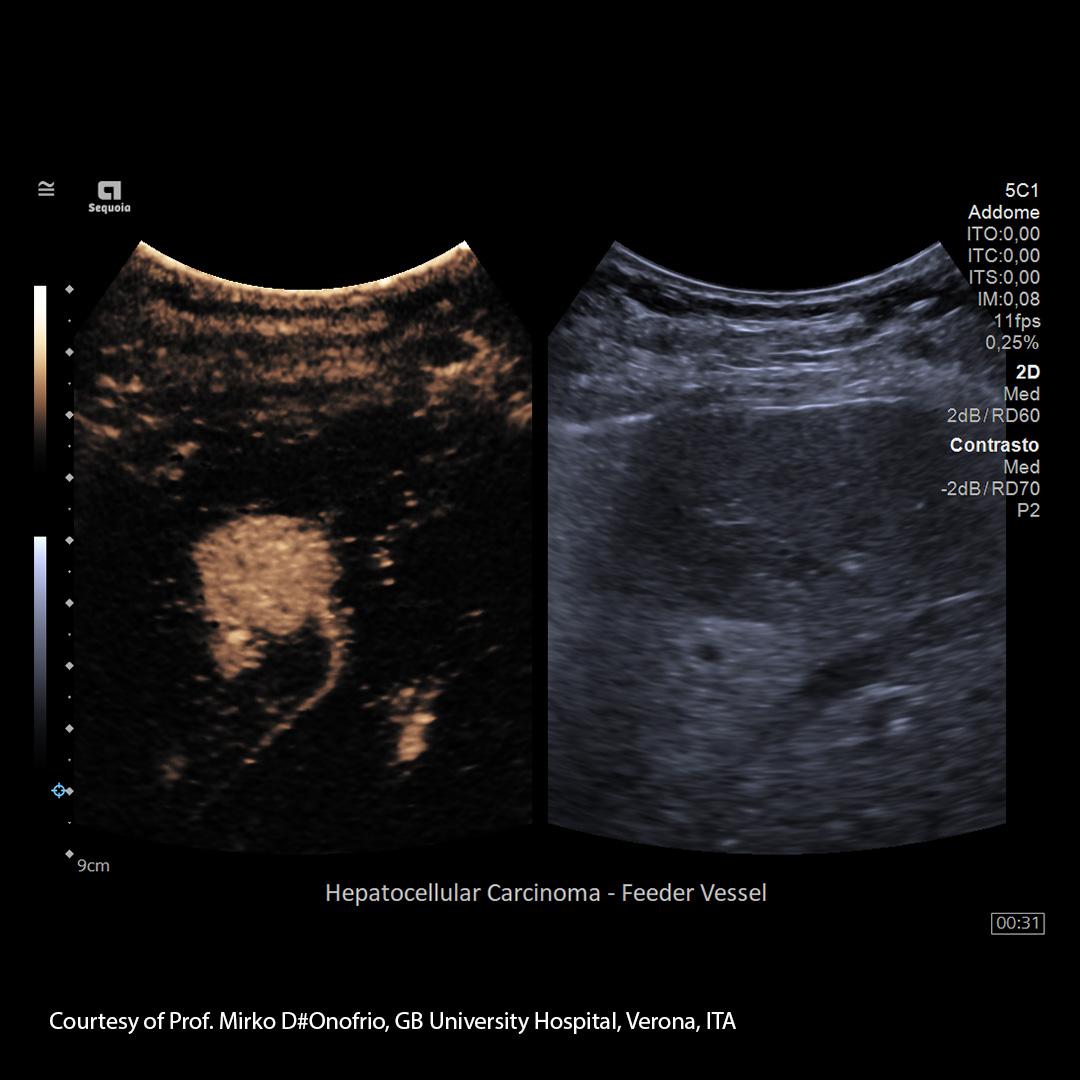

Imaging modalities for liver monitoring